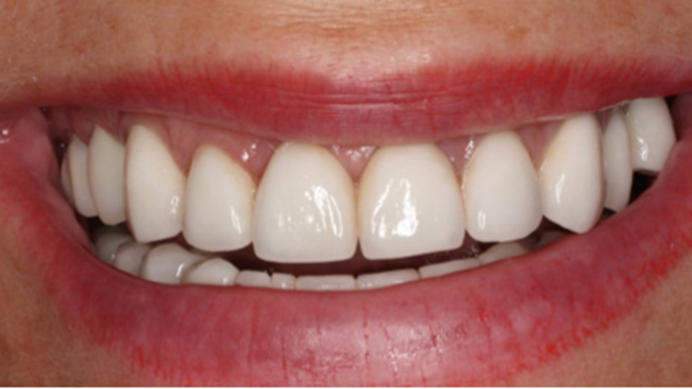

Clinical case: AnyRidge immediate loading

- Courtesy of Dr. Andres Paraud Freixas, Chile -

Keywords

AnyRidge, ISQ value, initial stability, immediate loading, KnifeThread, maxillary anterior, Mega ISQ, Dr. Andres Paraud Freixas

“Patient’s smile was recovered on the day of surgery

with reliable & highly-aesthetic results using AnyRidge & R2GATE. ”